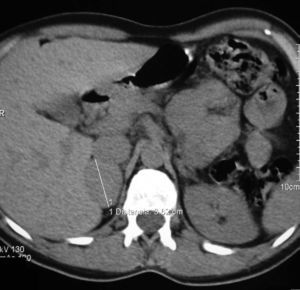

At the age of 40, she underwent work-up for dyspepsia and diarrhea, and an abdominal ultrasound examination revealed a right adrenal nodule. The patient reported sweating and heat intolerance over the previous two months, and her BP at the consultation was 158/92mmHg. There were no changes in routine laboratory tests. Urinary catecholamine and metanephrine tests were performed, with the following results: epinephrine, 117mcg/24h (NR: 0.5–20mcg/24h); norepinephrine, 424mcg/24h (NR: 14–80mcg/24h); metanephrine, 1386mcg/24h (NR: 86–320mcg/24h); and normetanephrine, 1720mcg/24h (NR: 129–400mcg/24h). An abdominal CT scan confirmed the presence of a homogeneous right adrenal nodule, 3.5cm in size, of 44 HU (Fig. 1). Meta-I-benzylguanidine (MIBG) scintigraphy showed uptake in the right adrenal gland. Laparoscopic surgery was performed after pharmacological alpha blockade with phenoxybenzamine 10mg/day. The pathological study was consistent with encapsulated pheochromocytoma.